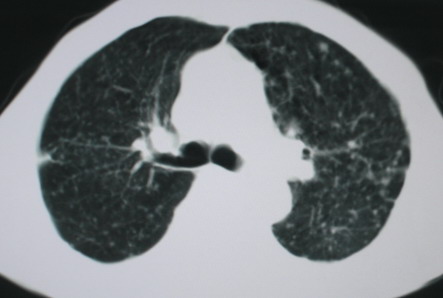

以下是引用卜一在2008-6-3 19:33:00的发言:[br]双肺结节,以双上肺分布为多,期间搀杂片状致密影及索条致密影。考虑:继发性肺结核伴血型播散可能性大。不除外肺泡ca的可能!另:椎体退变!

以下是引用panyishengct在2008-6-3 21:09:00的发言:[br]双上肺弥漫性小结节影,纵隔窗内钙化淋巴结影,考虑矽肺或/和tb可能性较大,不除外肺ca可能。腰椎考虑退变。 [br][br]